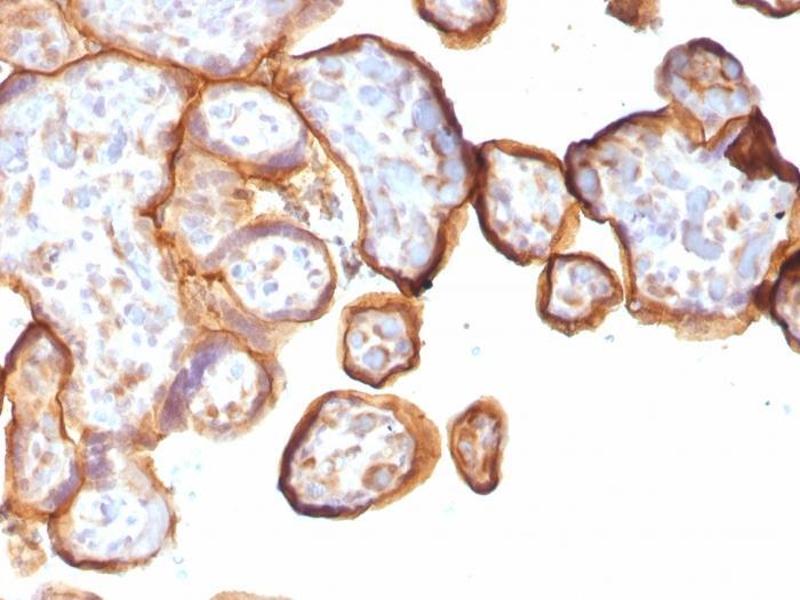

THBD 适用: 人 IHC 宿主: 小鼠 Monoclonal 141M unconjugated Recombinant Antibody

产品编号 ABIN7826102

100 μL (More quantities available)